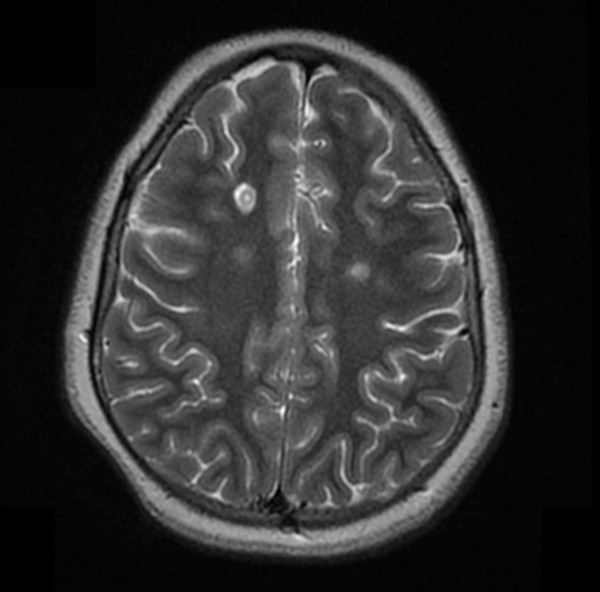

Se realiza una RM craneomedular. El estudio cerebral pone de manifiesto múltiples lesiones focales (aproximadamente 25, de entre 5 y 20 mm) predominantemente hiperintensas en secuencias T2. Afectan a la sustancia blanca yuxtasubcortical y periventricular de ambos hemisferios cerebrales, incluyendo el cuerpo calloso y el troncoencéfalo. Múltiples de las lesiones supratentoriales muestran una señal de resonancia heterogénea tanto en las secuencias T1 como T2, con un patrón interno en anillos concéntricos (patrón tipo Balo).

Se observa realce heterogéneo tras la administración de contraste en dos de las lesiones situadas en los hemisferios cerebrales, así como de la lesión que se sitúa en la hemiprotuberancia derecha afectando el trayecto intraparenquimatoso del nervio trigémino y comprometiendo también la emergencia del nervio facial derecho.